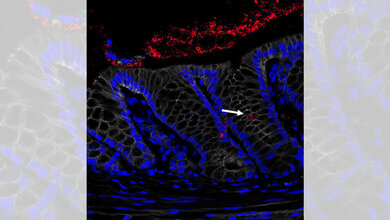

In Mäusen und an Geweben von Colitis-ulcerosa-Erkrankten zeigte sich, dass ein Botenstoff namens Prostaglandin E2 die Epithelzellen vor einer besonderen Form des Zelltods, der Nekroptose, bewahren kann. Prostaglandine sind hormonähnliche Botenstoffe und zeigen vielfältige Wirkungen im Organismus. Prostaglandine wie das Prostaglandin E2 werden im Körper bei Entzündungen freigesetzt. Wie sie Entzündungsprozesse regulieren, ist jedoch noch nicht vollständig verstanden.

In den vergangenen Jahren hatten die Forscherinnen und Forscher bereits zeigen können, dass die Fehlregulation der Nekroptose zu Zelltod und somit zu Löchern in der Darmbarriere führt. Prostaglandin E2 verhindert dies, indem es an auf den Epithelzellen vorhandene Rezeptoren mit der Bezeichnung EP4 bindet. Je mehr dieser Rezeptoren aktiviert werden, so das FAU-Team von der Medizinischen Klinik 1 – Gastroenterologie, Pneumologie und Endokrinologie – am Universitätsklinikum Erlangen, umso weniger Zellen sterben ab. Patientinnen und Patienten mit viel EP4 auf der Zelloberfläche zeigen einen milderen Krankheitsverlauf als Patienten mit wenig EP4.